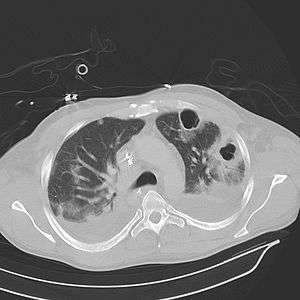

Computed tomography (CT) scan of chest showing bilateral pneumonia with abscesses, effusions, and caverns. 37-year-old male.

Lung abscesses are often on one side and single involving posterior segments of the upper lobes and the apical segments of the lower lobes as these areas are gravity dependent when lying down. Presence of air-fluid levels implies rupture into the bronchial tree or rarely growth of gas forming organism.